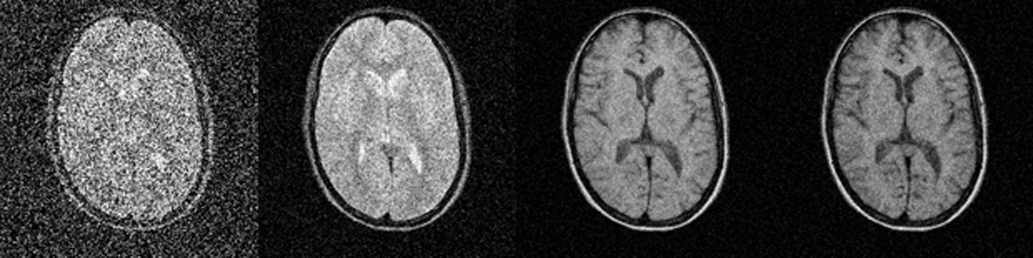

For many MR imaging data acquisitions, two data averages suffice for the cre­a­tion of images with good SNR. For n data-averaging runs, the net increase of S/N will be the square root of n. The S/N will, for example, increase by a factor of 2 if four data averages (numbers of excitations) are performed (Figure 09-07 and Figure 09-08).

Figura 09-07:

a 2; b 8; c 32; and d 128 data ave­ra­ges. The ‘polluting noise’ disappears slow­ly with higher num­ber of averages.